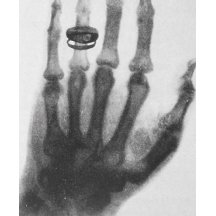

백지를 한 장 펴 놓고 맨 위에 ‘원자력’이라는 단어를 일단 써보자. 그리고 원자력이라는 말을 듣고 생각나는 것들을 써내려가 보자. ‘후쿠시마’, ‘원전’, ‘방사능’, ‘방사선’, ‘X선’, ‘퀴리부인’, ‘노원구 아스팔트’, ‘체르노빌’, ‘고...